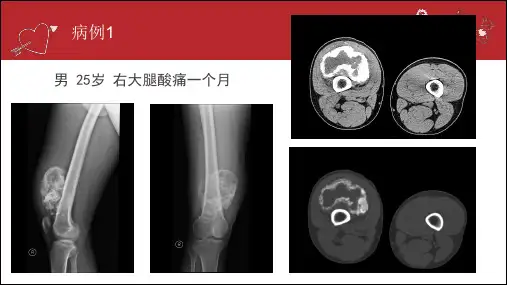

病例1男 25岁 右大腿酸痛一个月病例2男 13 右侧胫骨肿物骨软骨瘤的影像表现福建医科大学附属第一医院2016级 规培生 张欣悦骨软骨瘤(骨软骨性外生骨疣):指骨的表面覆以软骨帽的骨性突出物,多背离附近的关节生长。